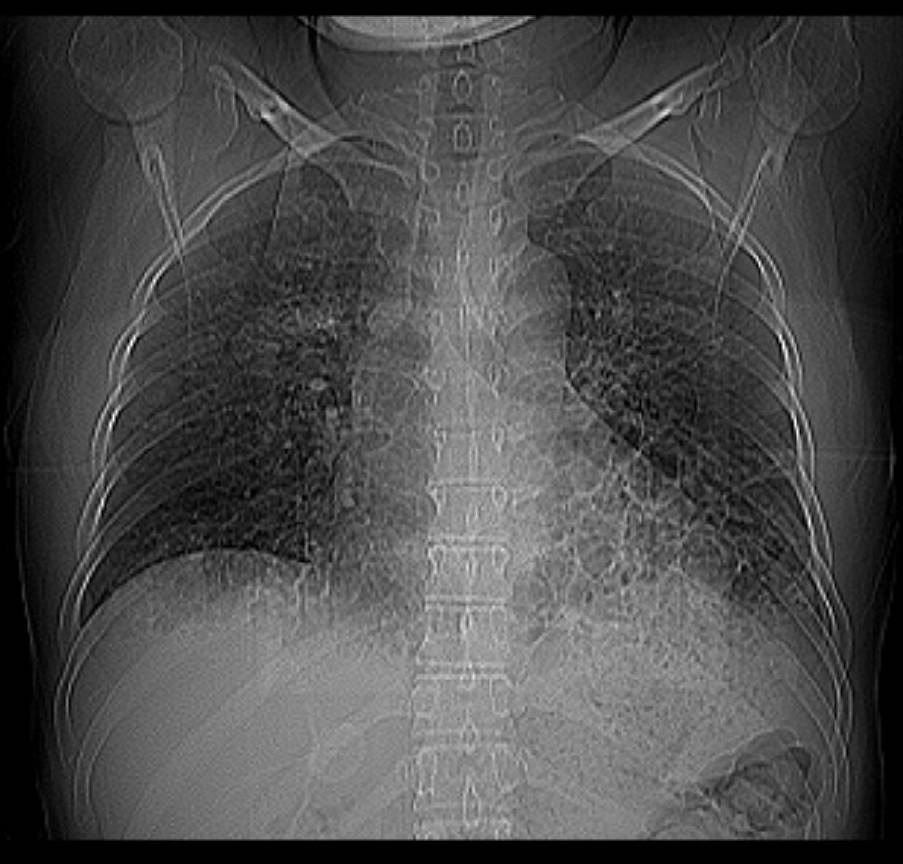

CL2630:典型支气管扩张并感染

三年前曾患支气管扩张,治疗后最近半年胸痛、多痰。

典型支气管扩张并感染

那是相当的不错“印戒”征